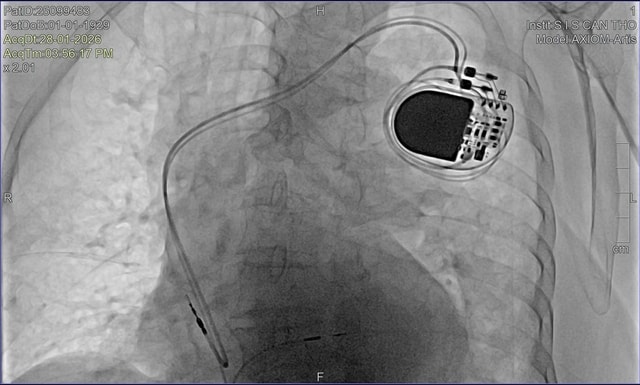

Trước tình thế đó, ê-kíp bác sĩ Bệnh viện Đa khoa Quốc tế S.I.S Cần Thơ đã nhanh chóng đặt máy tạo nhịp tạm thời để ổn định huyết động, đồng thời thực hiện các thăm dò chuyên sâu, trong đó có chụp mạch vành bằng DSA. Sau khi đánh giá toàn diện và hội chẩn, các bác sĩ thống nhất chỉ định cấy máy tạo nhịp vĩnh viễn bằng kỹ thuật bó nhánh trái – một phương pháp tiên tiến hiện chưa phổ biến rộng rãi.

BS.CKII Nguyễn Mạnh Cường – Phó khoa Nội Tổng hợp Bệnh viện S.I.S Cần Thơ cho biết, đây là bệnh nhân lớn tuổi nhất từng được bệnh viện thực hiện kỹ thuật này. Thách thức không chỉ đến từ tuổi cao mà còn ở đặc điểm rối loạn nhịp phức tạp, đòi hỏi thao tác chính xác và kiểm soát chặt chẽ trong suốt quá trình can thiệp.

Khác với cách tạo nhịp truyền thống, kỹ thuật bó nhánh trái giúp tái lập dẫn truyền điện học gần với sinh lý tự nhiên, bảo tồn chức năng co bóp của thất trái và giảm nguy cơ suy tim lâu dài. Với người cao tuổi, ưu điểm này càng có ý nghĩa khi mục tiêu điều trị không chỉ là kéo dài sự sống mà còn duy trì chất lượng sống.

"Ca can thiệp diễn ra thuận lợi. Sau thủ thuật, nhịp tim cụ ổn định, các triệu chứng giảm rõ rệt. Chỉ sau 4 ngày điều trị, cụ đủ điều kiện xuất viện trong sự xúc động của gia đình", BS. Cường thông tin thêm trong hôm nay (12/2).